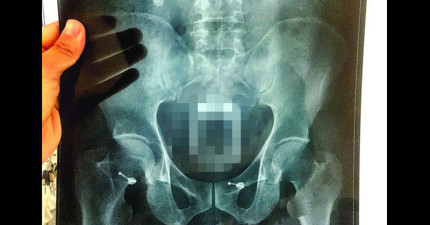

中國男子想出「超天才秘方」來治便秘,沒想到塞進去的東西讓醫生都嚇壞了!